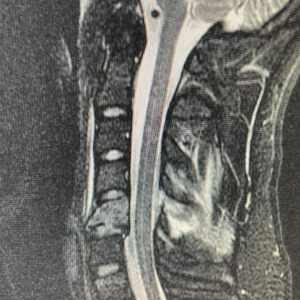

As a Neurosurgeon, spinal fractures of the neck from diving accidents are things that I see way too often. This young man dove from a boat into shallow water. He presented with some numbness in his arm and hand.

He had a fracture with the instability of his cervical spine at C5, requiring anterior and posterior surgery to decompress the nerve roots and stabilize his unstable cervical spine. He was lucky! His numbness improved, and he made a full recovery.